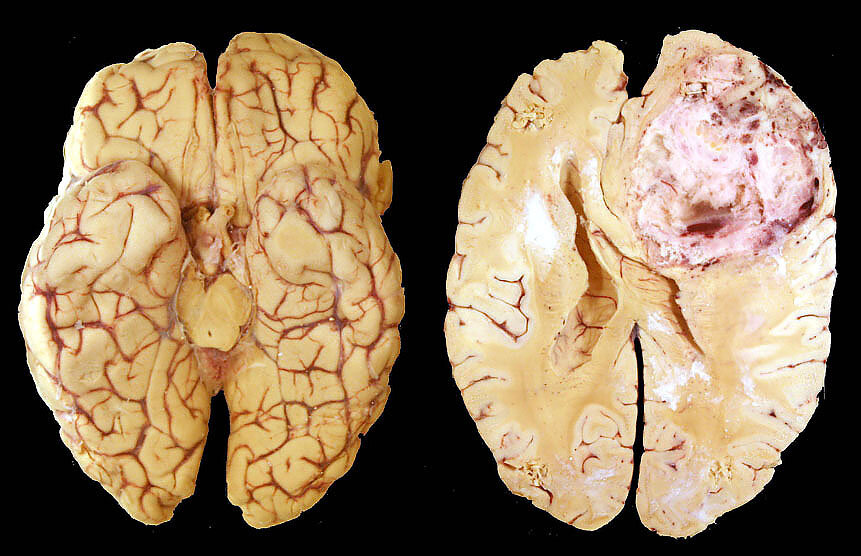

Глиобластома - самая злокачественная опухоль головного мозга, ее крайне трудно выявить на ранних стадиях, она достаточно быстро прогрессирует и плохо реагирует на лечение.

Этот рак чаще всего возникает в лобных и височных долях, происходит из глиальных клеток, расположенных хаотично. Вся клиническая картина зависит от локализации патологического процесса - на какие зоны головного мозга будет воздействовать опухолевые клетки, такие нарушения в организме и будут происходить.

При маленьких размерах опухоли никаких проявлений может и не быть - этим страшна глиобластома.